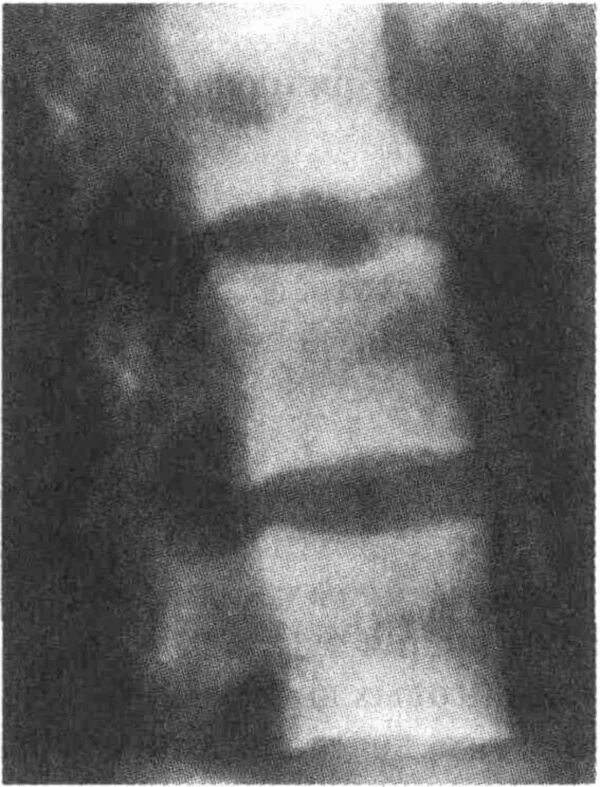

Остеосклероз грудного отдела